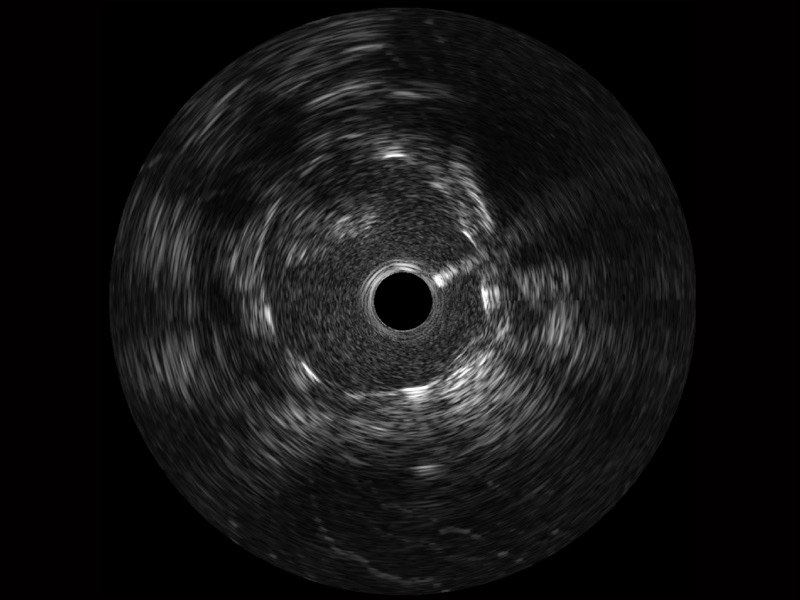

• 云顶集团官网宽频IVUS图像

• 传统IVUS图像

对比传统IVUS导管成像,云顶集团官网宽频IVUS图像的近场支架梁显影更细腻,远场中膜外血管仍清晰可辨,兼顾远中近,兼顾分辨力与穿透深度